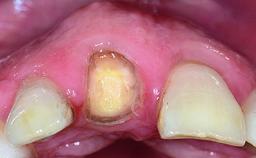

A 63-year-old male patient was referred for a consultation and treatment of partial edentulism in the maxilla. The patient presented with residual anterior teeth and declined a partial removable prosthesis. He reported that the maxillary posterior teeth had been extracted due to mobility and periodontal disease two months before the consultation. The patient’s chief complaint was that his residual maxillary teeth were mobile and that he was unable to chew. The patient’s desire was a stable and comfortable fixed maxillary rehabilitation. The patient was a light smoker (fewer than 10 cigarettes/ day), and his medical history was without significant findings. He was not on any regular medication at the time of consultation. The extraoral examination revealed a normal physiognomy with a correct distribution of the facial thirds. The patient presented a low lip line, and the transition line between teeth and soft tissues was not exposed during a forced smile.

Soft Tissue Contour and Volume Slightly compromised